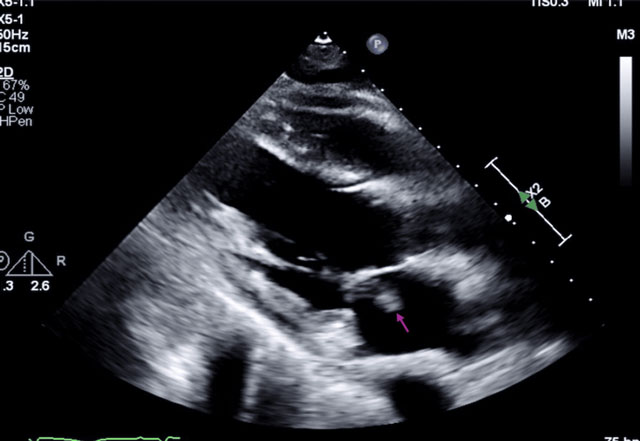

According to a recently published case report, a 53-year-old man was admitted after suffering a ventricular fibrillation arrest linked to a heart attack and acute headache. Further evaluation revealed a systolic murmur and a large vegetation on the mitral valve detected through echocardiography. Brain imaging showed multiple infarcts, while chest scans suggested septic emboli.